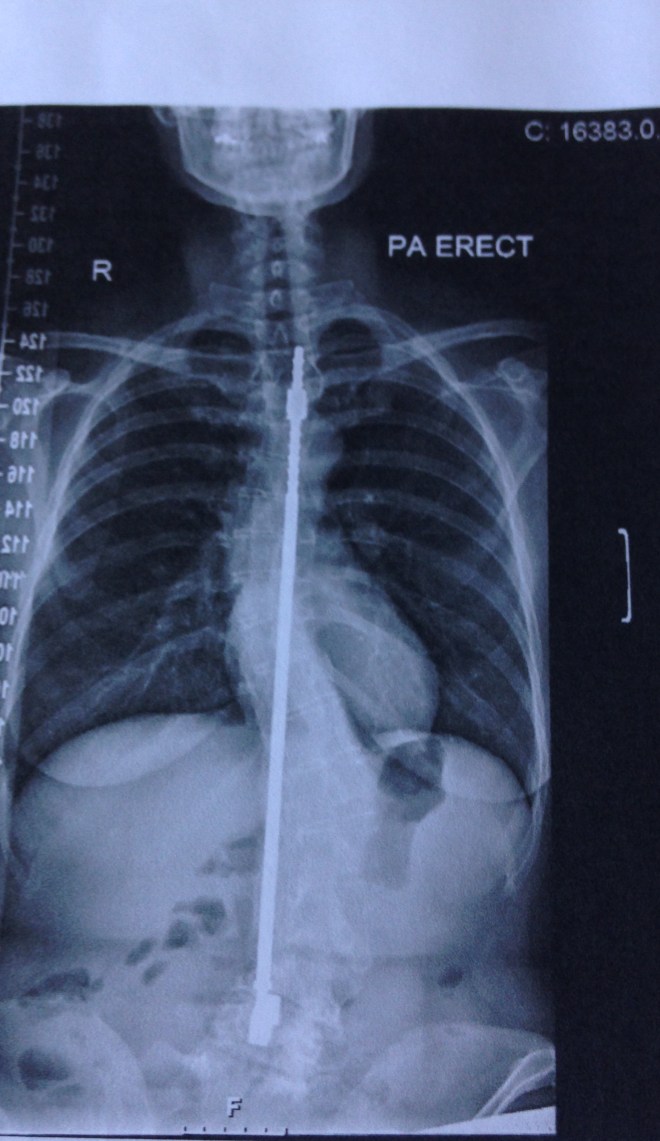

Monday has started off really well, I have lost another 4 pounds and another inch off of my waist on the 12 week MyBody challenge, I was so inspired that I did the MyPower Workout at 7.30 am and then took feisty daughter to school. Today is a day to celebrate, because on Monday May 14th 1979, I had a spinal fusion (large rod attached to my spine) to treat my scoliosis. For those of you that don’t know scoliosis is a curvature of the spine and mine was a lovely backwards S shape. The fun doesn’t stop there as the spine curves side-ways but also rotates, which means your hips, ribs and shoulders come out of alignment. I used to have trouble breathing and walking and my shoulders hurt a lot. I was told at the time that if I didn’t have the operation I would be in a wheelchair by the age of 21. I will be forever grateful to the brilliant Mike Edgar who operated on my back at Royal National Orthopaedic Hospital, Stanmore. Today my back feels great, I jive, I do zumba, go for long walks and now am doing the 12 week fitness challenge with Myleene Klass for the MailOnline http://www.dailymail.co.uk/…/Could-Myleene-Klass-body-12-we… . The RNOH has given me 39 years of health and movement – what a great hospital!